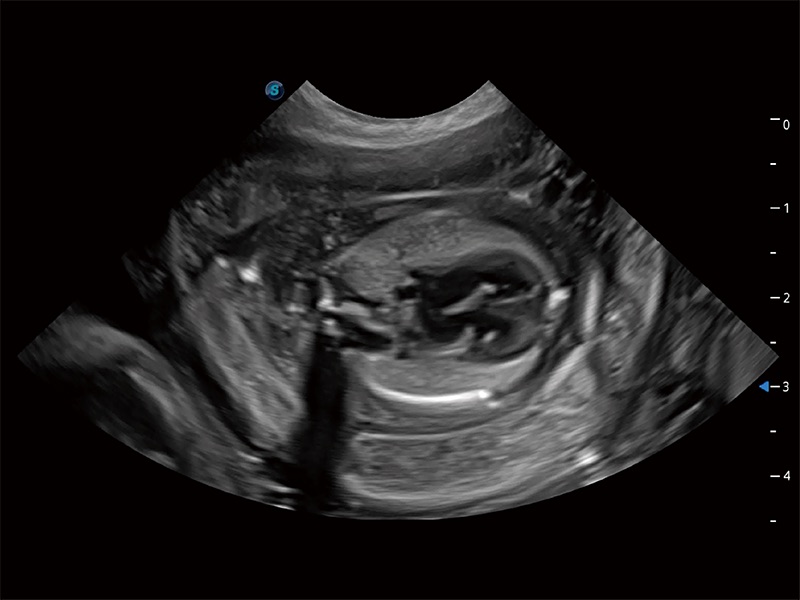

动物是人类最亲密的朋友和最值得信赖的伙伴。乐玩lewin国际也一直致力于探索动物专用的超声影像解决方案。全新推出的ProPet系列,是乐玩lewin国际在动物超声影像智能化、专业化、精准化的一次跨越式革新。动物不能用言语来表述自己的不适,通过超声影像,ProPet系列搭建了动物医生与不同物种沟通的“桥梁”,为动物医生注入了“治愈之力”。 ProPet 80 是乐玩lewin国际匠心打造的一款高端动物专用彩超,采用性能卓越的全新硬件架构,极大提升超声系统的运行效率和数据处理能力,帮助动物医生从容应对日益增多的挑战性病例和日益多样化的临床需求。

高性能和先进的临床应用工具可以为动物医生提供临床信心。ProPet 80 搭载了先进的腹部和浅表应用工具,帮助医生在日常临床实践中发挥前所未有的作用。

ProPet 80 全新的动物超声智能软件和丰富的探头群,为动物医生提供了高清晰度和精细分辨率的图像,无论在宠物、马科、畜牧还是实验室动物等应用中都可以轻松应对,为您的日常工作带来满意的体验。